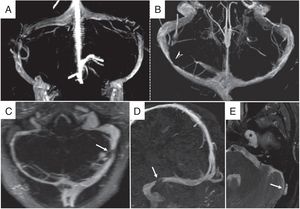

Estenosis de senos transversosLa estenosis de senos transversos presenta una prevalencia de hasta el 90% en pacientes con HII5. La localización más frecuente es en la región distal de los senos transversos o en su unión con los senos venosos sigmoides, de manera uni- o bilateral (fig. 4)23,24.

Estenosis de senos venosos transversos. Angio-RM venosa con contraste, reconstrucciones volumétricas 3D coronal (A) y transversal (B). A y B) Estenosis venosa extrínseca. A: estenosis bilateral típica en la región distal de los senos transversos. B: estenosis unilateral en el tercio medio del seno transverso derecho. C-E) Estenosis venosa intrínseca por granulación aracnoidea. C: angio-RM venosa con contraste con reconstrucción de máxima intensidad de proyección (MIP) en plano transversal en la que se visualiza hipoplasia del seno venoso transverso derecho y pequeño segmento estenótico significativo en tercio distal de seno transverso izquierdo. D: reconstrucción MIP en plano parasagital que demuestra los bordes bien delimitados de la estenosis (flecha blanca). E: secuencia STIR transversal en la que se identifica una granulación aracnoidea como causa de la estenosis (flecha blanca). Obsérvese también un meningocele del cavum de Meckel (asterisco) asociado a la HII.

La venografía por RM con contraste y técnica ATECO (Auto-Triggered Elliptic Centric-Ordered imaging) disminuye la pérdida de señal por artefactos con respecto a la técnica usada clásicamente (time-of-flight, venografía por RM) y permite una mejor detección de la estenosis de senos venosos, con una sensibilidad y especificidad del 93%5. Las estenosis de senos venosos pueden ser intrínsecas o extrínsecas.

Estenosis intrínseca de senos transversosSe han descrito alteraciones en los senos venosos que causan defectos focales en el relleno intraluminal, producen estenosis intrínseca y podrían contribuir a la producción de hipertensión intracraneal. Estas alteraciones incluyen septos, granulaciones aracnoideas y proyecciones de la matriz aracnoidea y el espacio subaracnoideo en la pared de los senos venosos durales24. Las granulaciones aracnoideas han sido descritas en un 24% de las tomografías computarizadas (TC) y en un 13% de los estudios de RM con contraste en poblaciones normales y aumentan en número con la edad. Frecuentemente se observan en los senos transversos y sigmoideos24,25.

Estenosis extrínseca de senos transversosSe trata de una estenosis de la luz de los senos venosos por compresión secundaria al aumento de PIC, que produce un “estado de colapso venoso automantenido”2. Este estado es considerado causa y consecuencia del aumento de PIC. El LCR se reabsorbe de forma pasiva a través de los espacios perivenulares y en las granulaciones aracnoideas hacia los senos venosos intracraneales. Una estenosis en un seno transverso dominante o una estenosis bilateral pueden dificultar el drenaje venoso y producir hipertensión venosa. Esta hipertensión dificulta y reduce la absorción de LCR causando aumento de la PIC y mayor compresión aún de los senos venosos2,3,26.